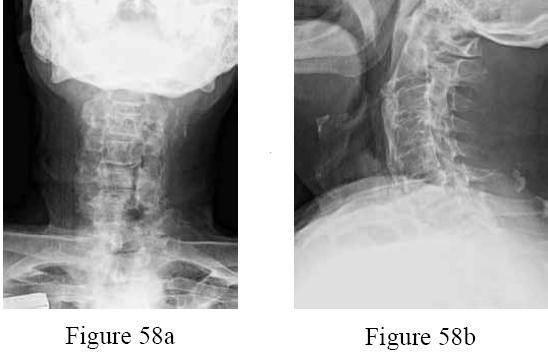

A 6-year-old boy presents with a low posterior hairline, short webbed neck, and limited cervical range of motion. Radiographs show multiple fused cervical vertebrae. Which of the following systems is most crucial to evaluate in this patient?

Explanation

A 5-year-old boy presents with a short neck, low posterior hairline, and limited cervical range of motion. Radiographs reveal congenital fusion of the C3-C4 and C5-C6 vertebral bodies. Which of the following is the most appropriate next screening test to evaluate for commonly associated anomalies?